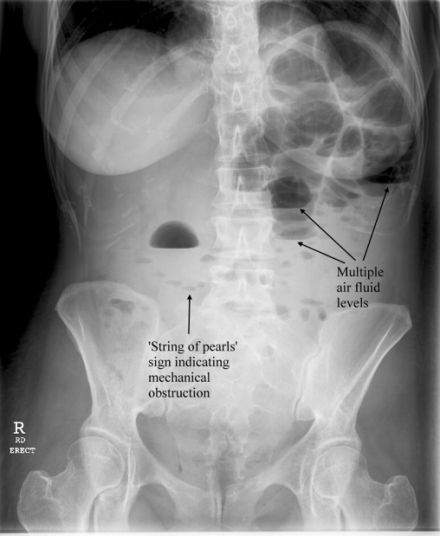

- Plain Radiographs

- Special Considerations on Radiography